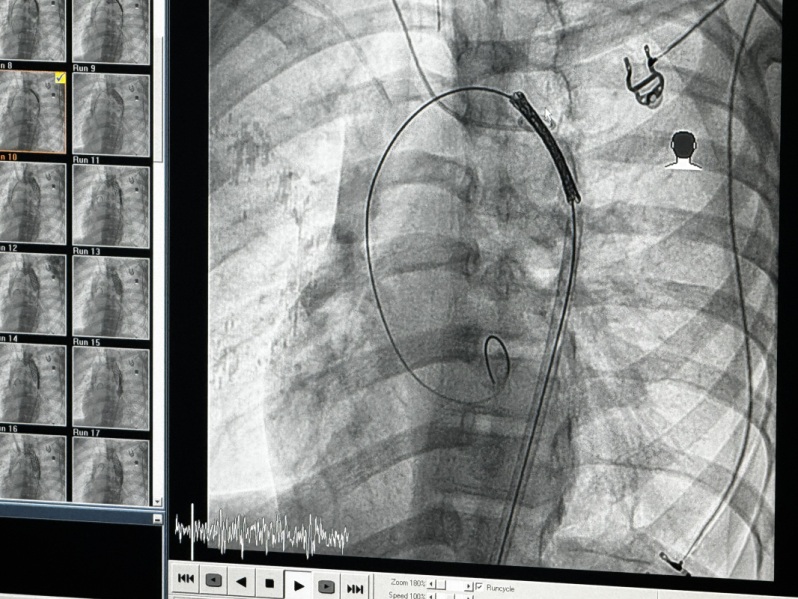

Врач пояснил, что при таком диагнозе 80% пациентов погибают в первые сутки после травмы. Для того чтобы спасти ребёнка было необходимо исключить псевдоаневризму из кровотока – для этого в условиях рентген-операционной в аорту требовалось имплантировать стент-графт – металлический каркас, покрытый специальным герметичным полимером. Несмотря на то, что подобные повреждения у детей огромная редкость, у врачей Педиатрического университета были необходимые компетенции и опыт, ранее они уже спасали подростка посттравматическим расслоением грудной аорты.

– Так как повреждённый участок был протяженным, то мы изначально понимали, что одного стенда для его перекрытия нам не хватит. Потребовалось имплантировать три стент-графта, с помощью которых мы полностью перекрыли аневризматическое расширение и выключили псевдоаневризму из кровотока. Теперь аневризматический мешок не заполняется и разорваться, следовательно, не может, – рассказал рентгенэндоваскулярный хирург Педиатрического университета Роман Громовой. |

Отметим, что правильно позиционировать стенты было сложнейшей задачей: стенки повреждённого сосуда были истончены, и одно неверное движение могло привести к катастрофе.